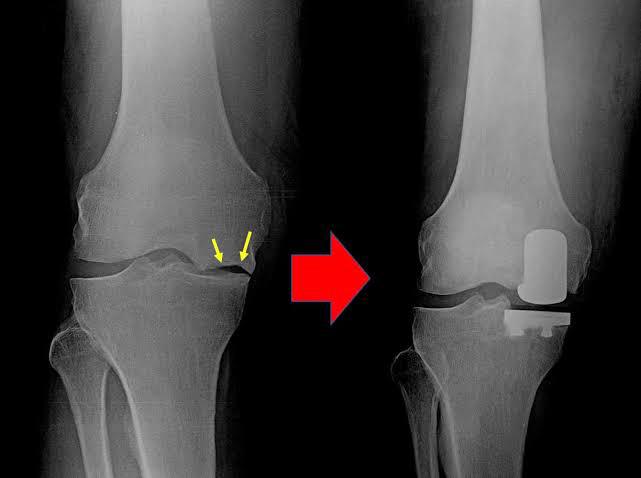

Muscle-Sparing Joint Replacement

Total Knee Replacement (TKR)

Partial Knee Replacement